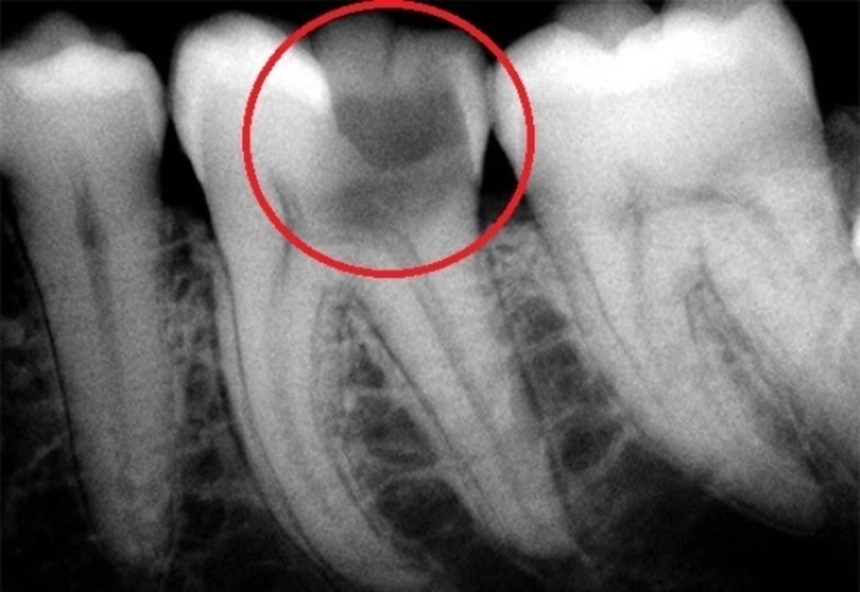

Вскрытия каналов

Вскрытия каналов 108 фото